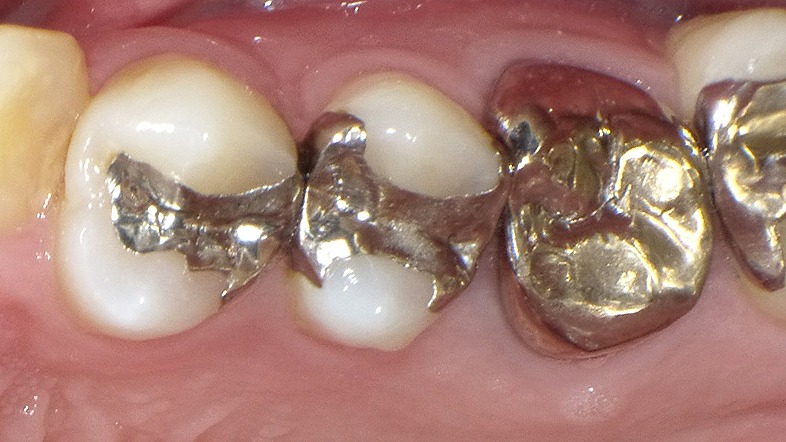

上顎6番の銀歯の内部で神経近くまで虫歯(二次カリエス)が進行している様子を示すレントゲン画像です。

銀歯と歯との間にすき間が生じると、その下で虫歯が広がりやすく、治療後に「しみる」「痛む」といった症状の原因になります。虫歯が神経付近まで達すると、再治療や根管治療が必要になることがあります。